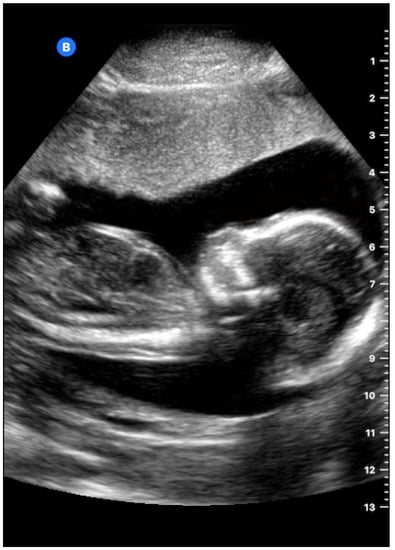

- Stephens, D.N.; Truong, U.T.; Nikoozadeh, A.; Oralkan, O.; Seo, C.H.; Cannata, J.; Dentinger, A.; Thomenius, K.; Rama, A.d.l.; Nguyen, T.; et al. First In Vivo Use of a Capacitive Micromachined Ultrasound Transducer Array—Based Imaging. J. Ultrasound Med. 2012, 31, 247–256. [Google Scholar] [CrossRef] [PubMed]

- Butterfly Network. 2019. Available online: www.butterflynetwork.com/clinical/ob (accessed on 11 January 2019).